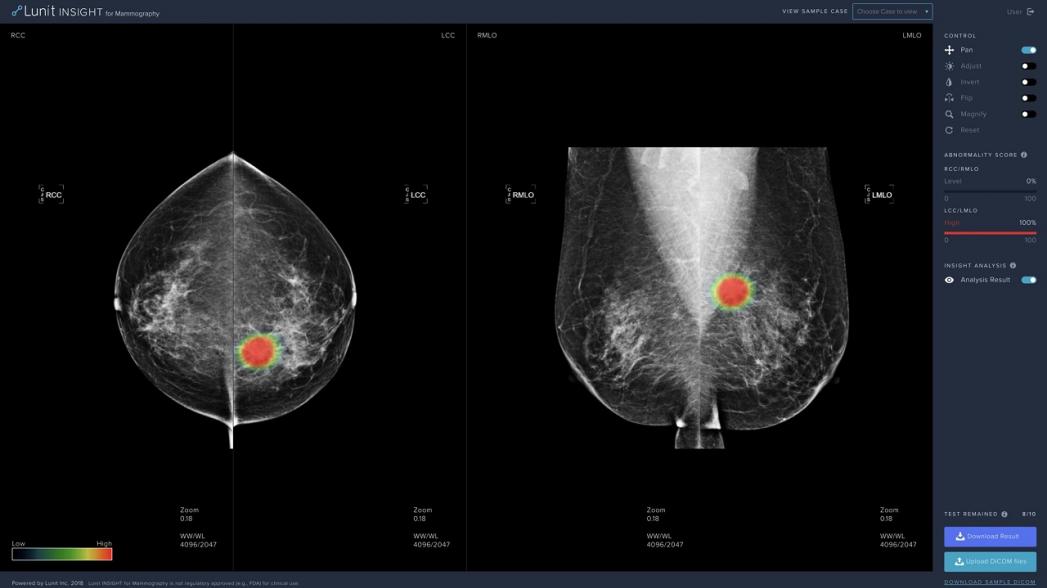

Lunit INSIGHT MMG анализирует маммографические снимки с точностью до 97%, обеспечивая локализацию участков, подозрительных с точки зрения рака молочной железы. Она также оценивает аномалии, отражая вероятность наличия в этих местах раковых поражений.